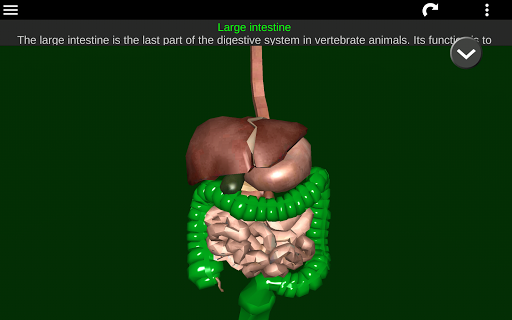

* Sistem pencernaan, termasuk lambung, usus kecil, usus besar, dan animasi sistem ini.